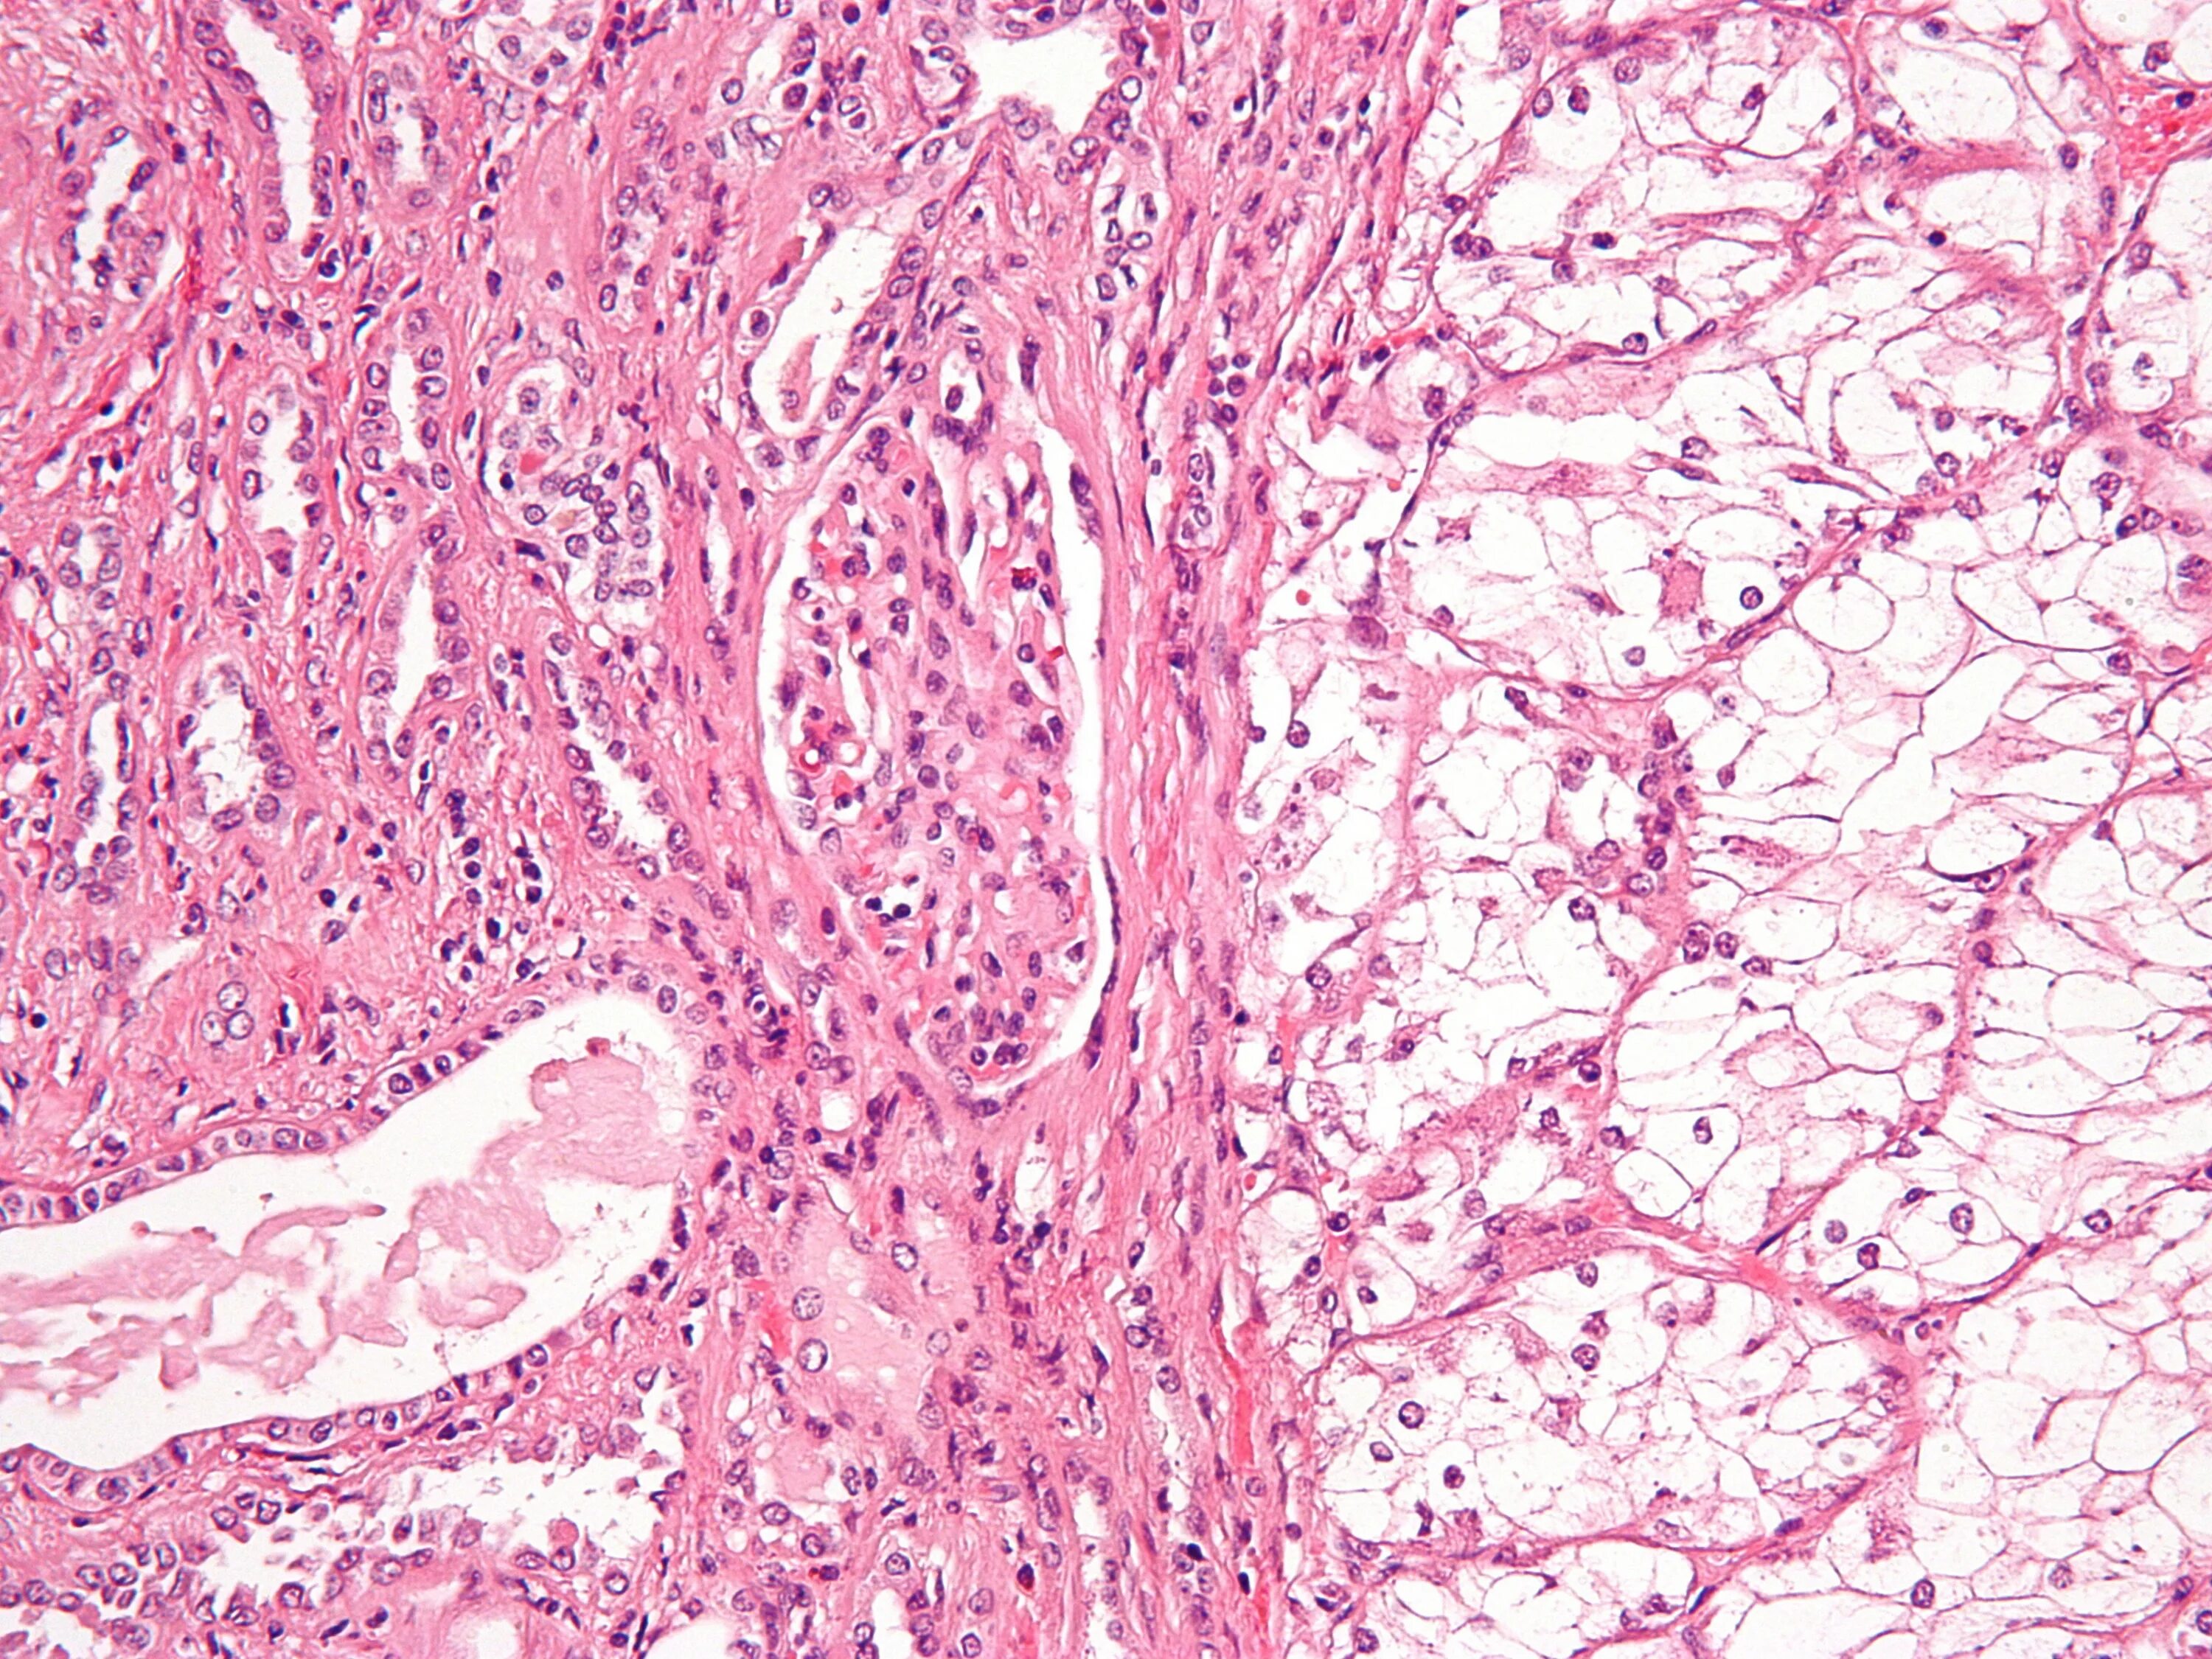

Гистологические варианты